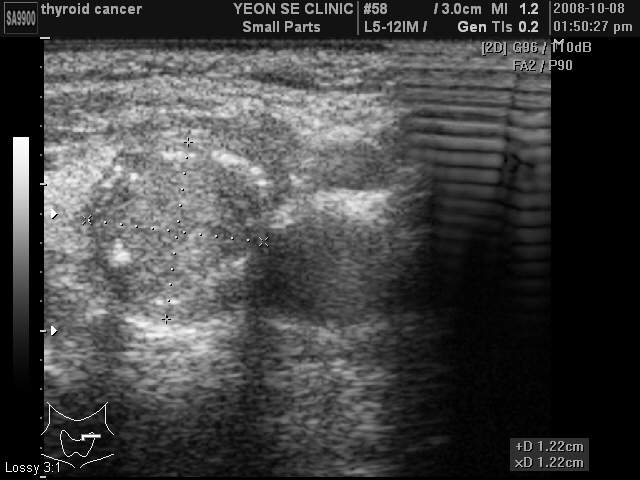

Ultrasonographic data of our patients

Thyroid ca...